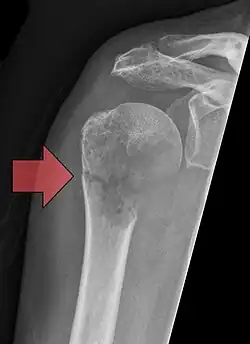

Pathological fracture of the humerus in a patient with metastasis of renal cell carcinoma

A pathologic fracture is a bone fracture caused by weakness of the bone structure that leads to decrease mechanical resistance to normal mechanical loads.[1] This process is most commonly due to osteoporosis, but may also be due to other pathologies such as cancer, infection (such as osteomyelitis), inherited bone disorders, or a bone cyst. Only a small number of conditions are commonly responsible for pathological fractures, including osteoporosis, osteomalacia, Paget's disease, Osteitis, osteogenesis imperfecta, benign bone tumours and cysts, secondary malignant bone tumours and primary malignant bone tumours.

Pathological fractures present as a chalkstick fracture in long bones, and appear as a transverse fractures nearly 90 degrees to the long axis of the bone. In a pathological compression fracture of a spinal vertebra fractures will commonly appear to collapse the entire body of vertebra.